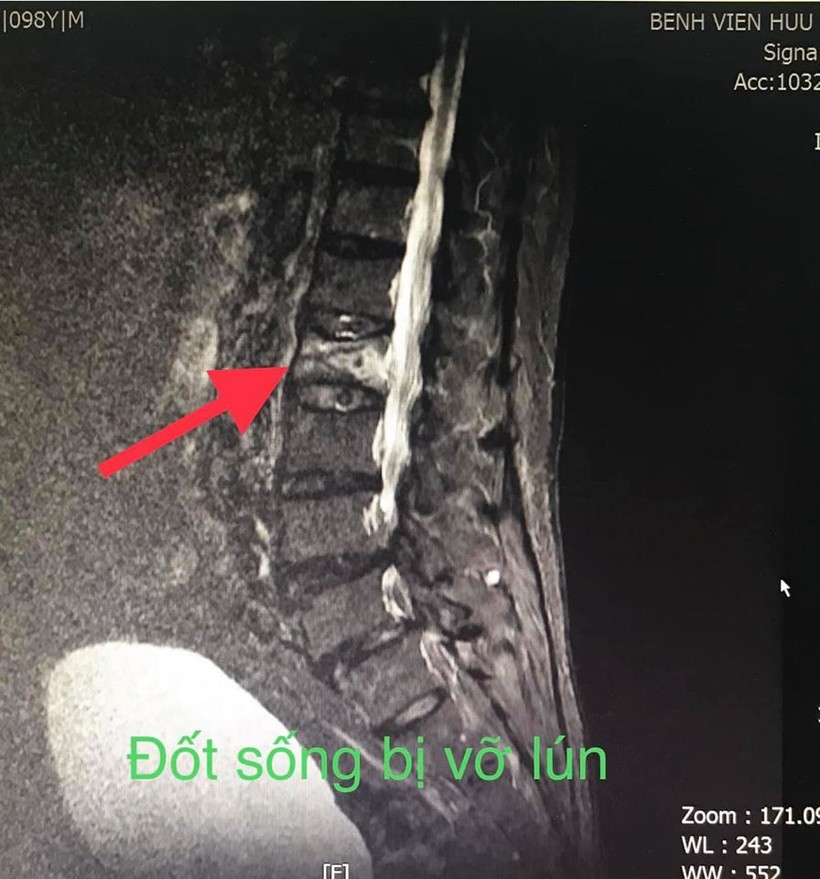

Sau khi thăm khám, các bác sĩ xác định bệnh nhân bị vỡ lún đốt sống L2.

Đốt sống bị vỡ lún của bệnh nhân. Ảnh: BVCC